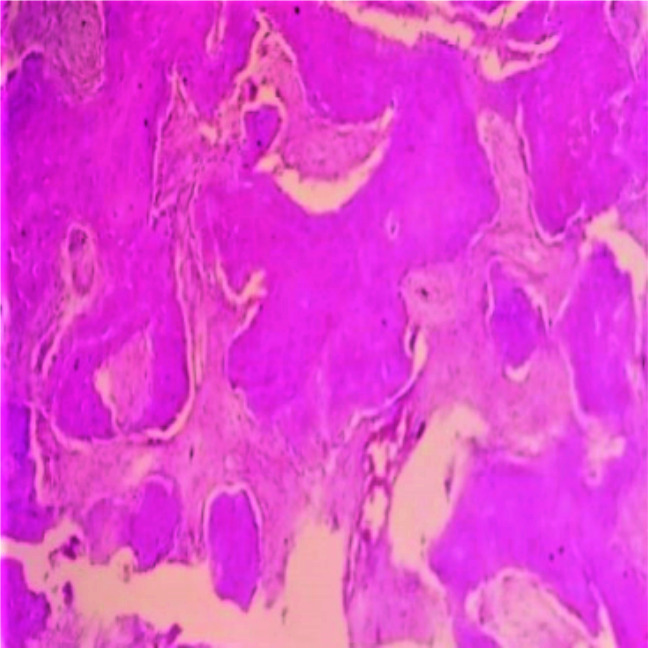

Materials and method: This was a retrospective study where hematoxylin and eosin (H&E) slides and archival records of fibrous dysplasia (FD) and ossifying fibroma (OF) cases were reviewed. The sections were assessed for permeation of marrow spaces, stromal growth pattern, cytologic atypia, mitotic activity, and pattern of bone growth, which are parameters for diagnosing LGCOS. The predictive histologic index of malignancy (PHIM) was determined by a sum of the scores and graded as 0=nil, 1=low, 2 & 3=moderate, and 4 & 5=high. Data were presented using descriptive analysis.

Results: Ninety-three cases of FLs met the inclusion criteria, consisting of 40(43%) cases of FD and 53(57%) cases of OF. The peak age of presentation for FD and OF was 2nd and 3rd decade. There was a female preponderance of 1:1.6. The maxilla was the most common site affected by FD, while the mandible was most commonly affected by OF. For FD cases, the PHIM was moderate in 10(25%) cases and low in 21(52.5%) cases. Similarly, for OF cases, 30(56.6%) cases had low grade PHIM while 10(17%) cases had moderate grade PHIM.